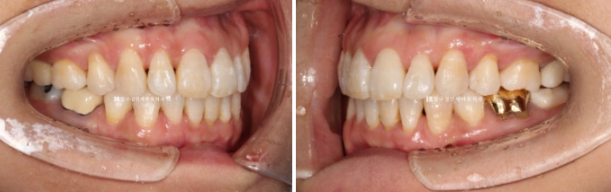

배열에서 가장 많이 벗어난 덕분에 잇몸이 유독 내려갔던 치아를 자세히 보겠습니다.

23.07~24.05

잇몸 퇴축이 회복이 되어 치아뿌리 노출이 줄었습니다.